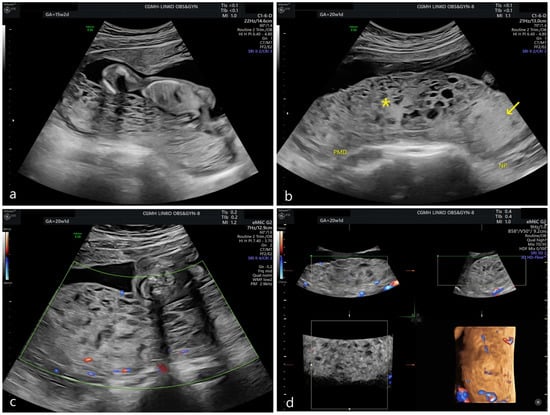

Prenatal Diagnosis of Placental Mesenchymal Dysplasia with 46, X, Isochromosome Xq/45, X Mosaicism

2.1. Patient